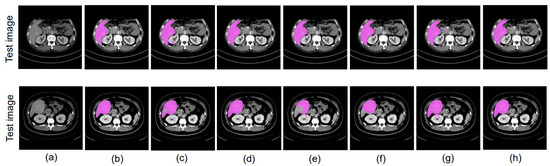

4.8. Ablation Study

4.8.1. Different Datacenter and Same Phase

4.8.2. Same Datacenter and Different Phase

4.8.3. Different Datacenter and Different Phase